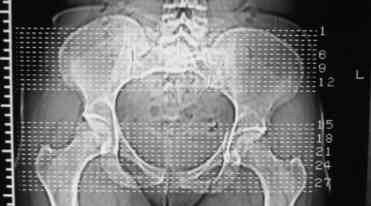

В больнице вправили вывих бедра, три недели на вытяжении. Беспокоят боли в левом тазобедренном суставе и левом крестцово-подвздошном сочленении. Ходит с тростью. Снимок - в приложении. Направил на КТ, заключение: разрыв симфиза и левого крестцово-подвздошного сочленения, переломы крыши и заднего края вертлужной впадины, горизонтальной ветви лонной кости слева.

Уважаемый д-р Булахтин, на мой взгляд единственное повреждение требующее синтеза - застарелый разрыв лона. Низкий перелом передней колонны безопасен, повреждения свода не вижу, неясно что было сзади (скорее боковая масса)лучше сделать обзорный снимок прямой и Inlet.

Очень похоже на повреждение от бокового сжатия.

Признаков разрыва сочленения не вижу, м.б. контрлатеральный перелом боковой массы.

Если был задний вывих, то повреждение должно локализоваться сзади. В данном случае перелом спереди, как результат сдавления лонного сочленения.